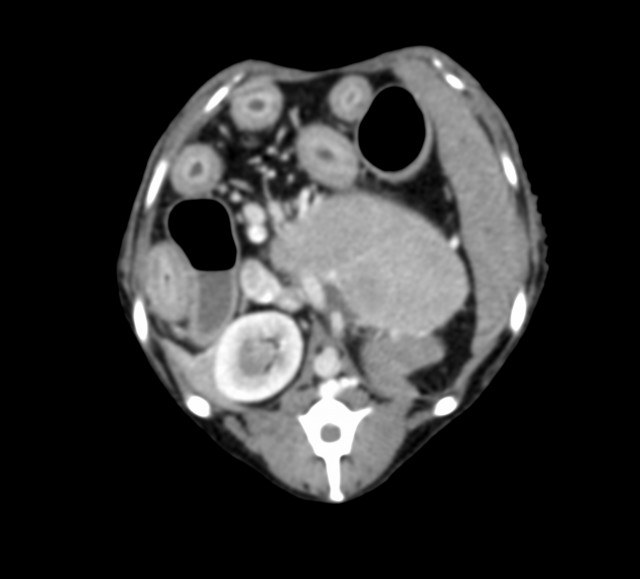

CT検査では、腫瘤は脾臓と接しているものの脾臓からの発生ではなく、その他の腹腔内臓器で唯一、左側の副腎が確認できないため副腎腫瘤と診断した。

腫瘤は大きく、かつ後大静脈との癒着も疑われるため、手術による摘出は極めて困難であると判断した。